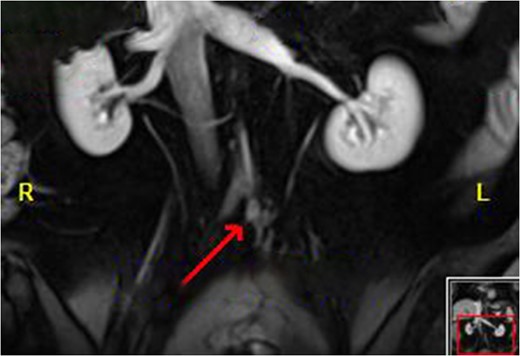

Magnetic resonance imaging (MRI) after the initial chemotherapy cycle demonstrated a liver segment VIII 13-mm metastasis and indeterminate 5-mm lesions in segments VI and IV. Interventional radiology services performed a right portal vein embolization. On subsequent postembolization MRI, hepatic lesions were indiscernible, and liver remnant volumetrics increased from 21 to 35%.

Neoadjuvant therapy was completed 1 month before surgical intervention. The patient underwent bilateral ureteral stents placement and an exploratory laparotomy in the lithotomy position. Intraoperative ultrasonography localized the tumor without showing any unexpected lesions. A right extended hepatectomy proceeded in the standard manner (Figs 3 and 4).